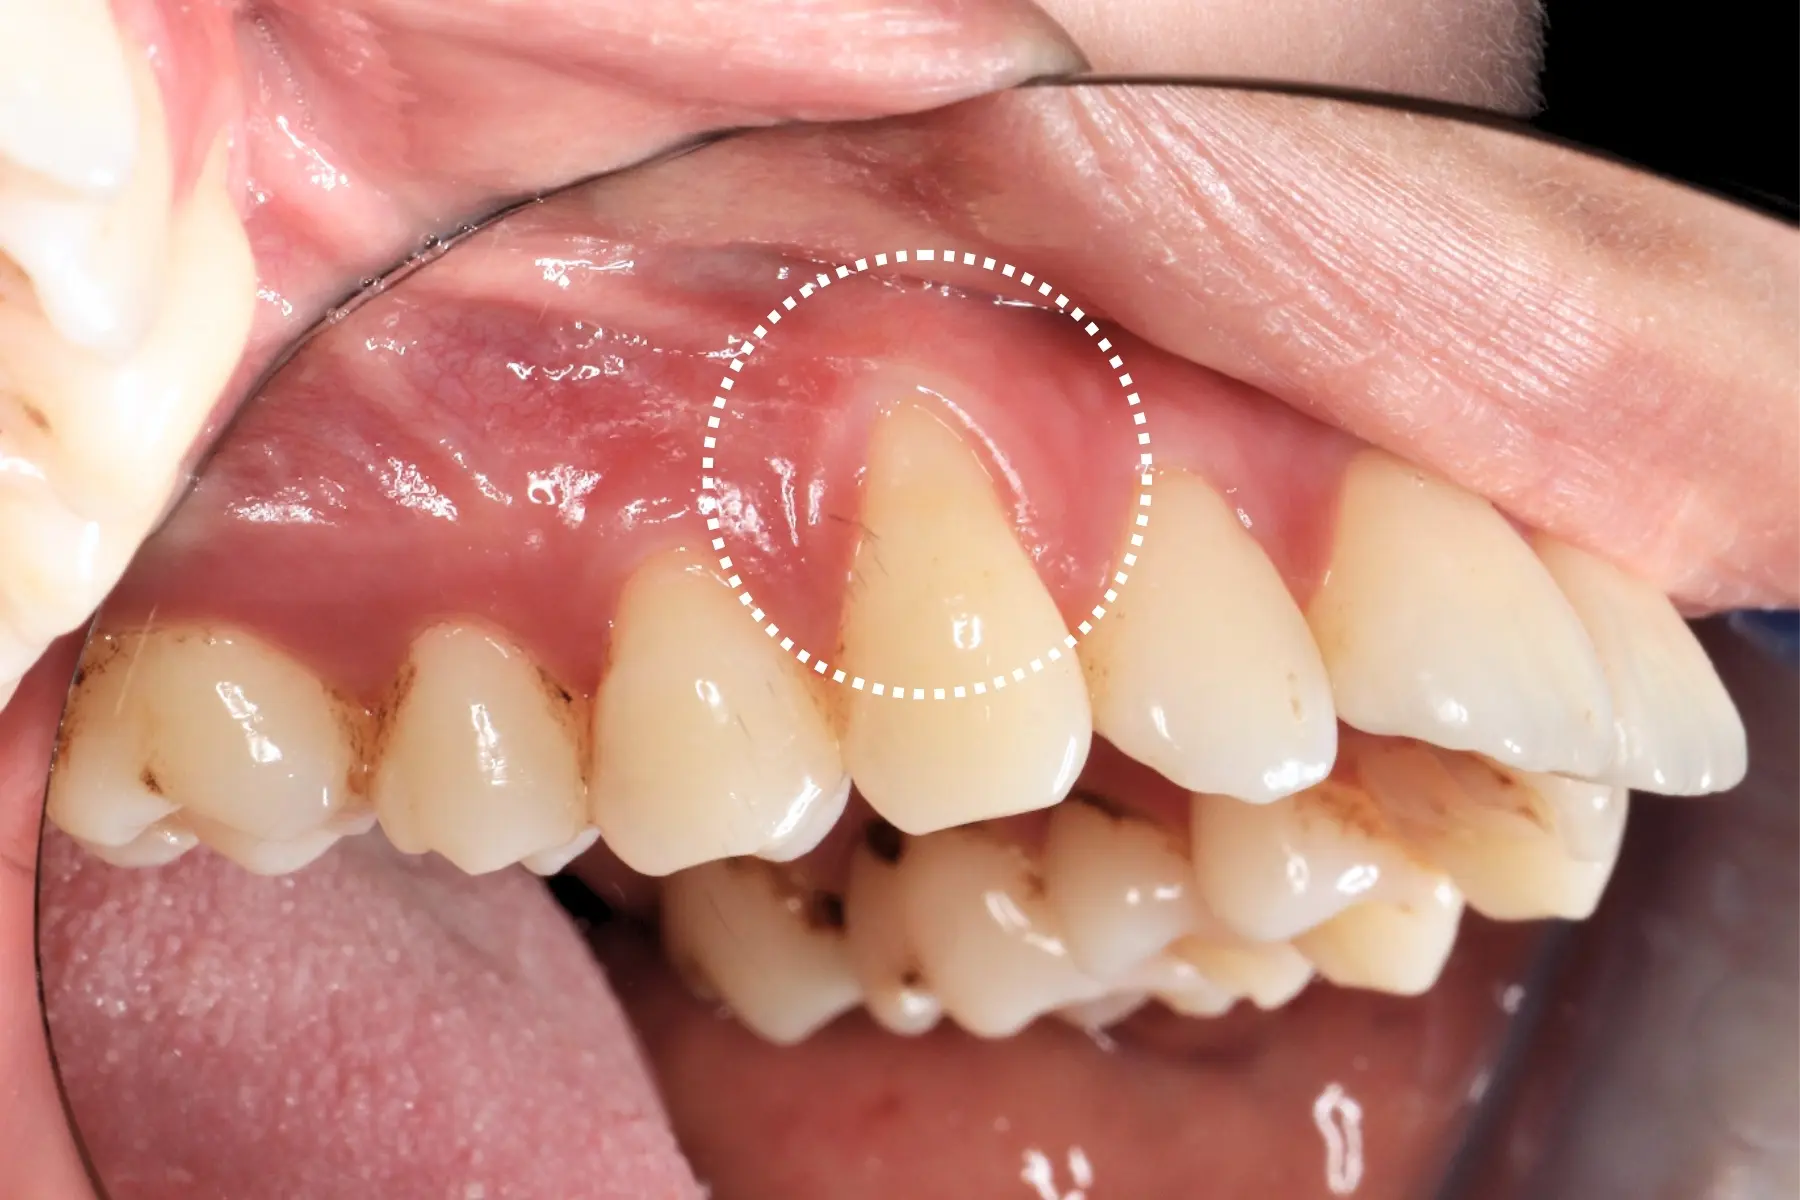

• 術前 42

術後 40

牙周治療

主治醫師

• 鍾國耀

治療時間

三次療程

主訴

牙齦紅腫出血、牙縫容易塞食物